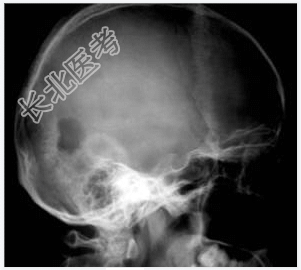

- [材料题] 病历摘要:男性,20岁。

主诉:发现头皮软组织肿物3个月。

现病史:三月前发现左枕部软组织轻微突起伴隐痛,到当地医院检查发现左枕部颅骨骨质缺损,未作具体治疗,现觉头皮肿物增大,时伴有气促、头痛。

专科检查:左颞枕部软组织略膨起,较软,各项病理反射(-)。